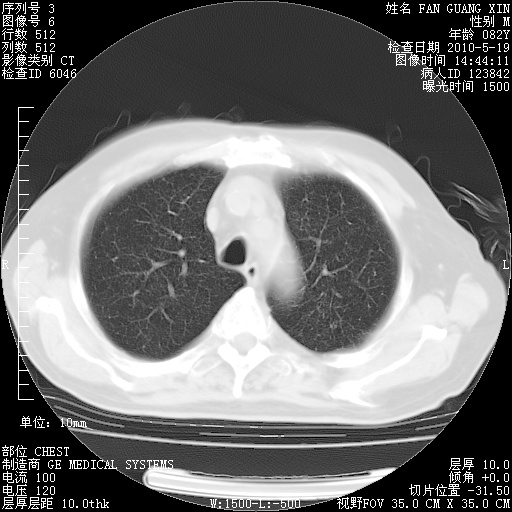

复查肺部CT,明显好转。为什么发热呢?

治疗3周后的肺部CT